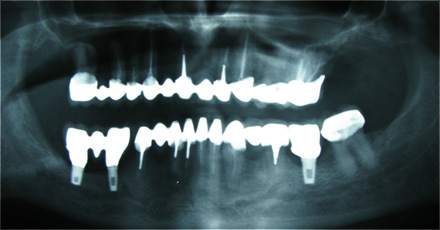

Caso 3 - Desdentado total reabilitado com prótese acrílica removível inferior, barra e clips para retenção e estabilidade

![]() |

![]() ![]() |